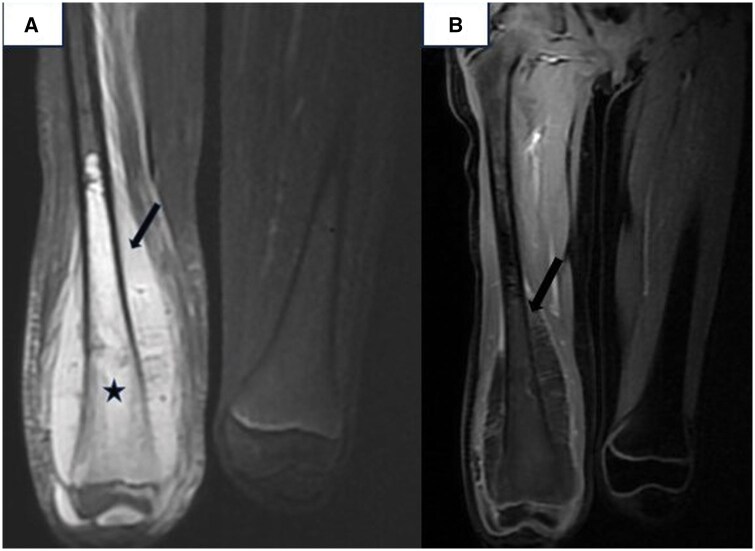

Chondromyxoid fibroma-like osteosarcoma (CMF-OS) is an exceptionally rare and low-grade variant of osteosarcoma, as classified by the World Health Organization. Misdiagnosis is common in CMF-OS, often leading to delays in definitive surgical intervention. CMF-OS exhibits variable imaging features, frequently mimicking chondromyxoid fibroma. It may present as osteolytic, osteogenic, or expansive lesions, often associated with soft tissue invasion, cortical disruption, and occasionally a periosteal reaction. Cases have been reported in diverse anatomical locations, including the craniofacial region and bones of the lower limbs. Histologically, CMF-OS is distinguished by its unique mucoid appearance, characterized by loose aggregates of stellate and spindle-shaped tumour cells embedded within a highly myxoid stroma. Surgical resection remains the cornerstone of treatment for CMF-OS, emphasizing the importance of accurate diagnosis to facilitate timely and appropriate management.